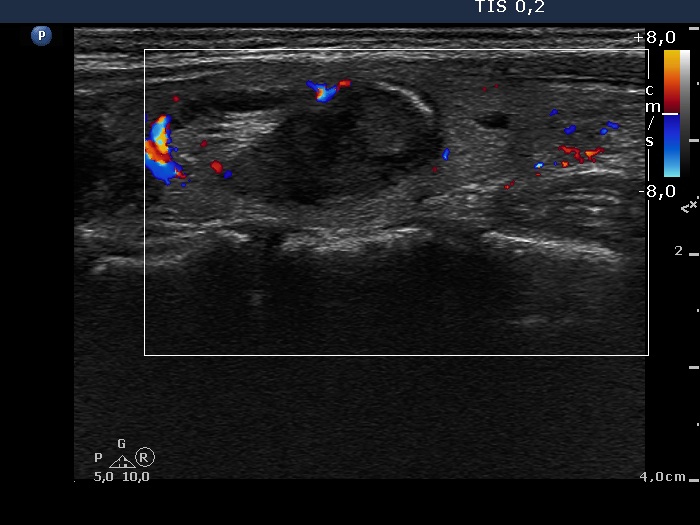

Six months after the therapy (ultrasonographic picture 3)

Right lobe, longitudinal scan, color Doppler mode. Signs of a type 2 vascular pattern.